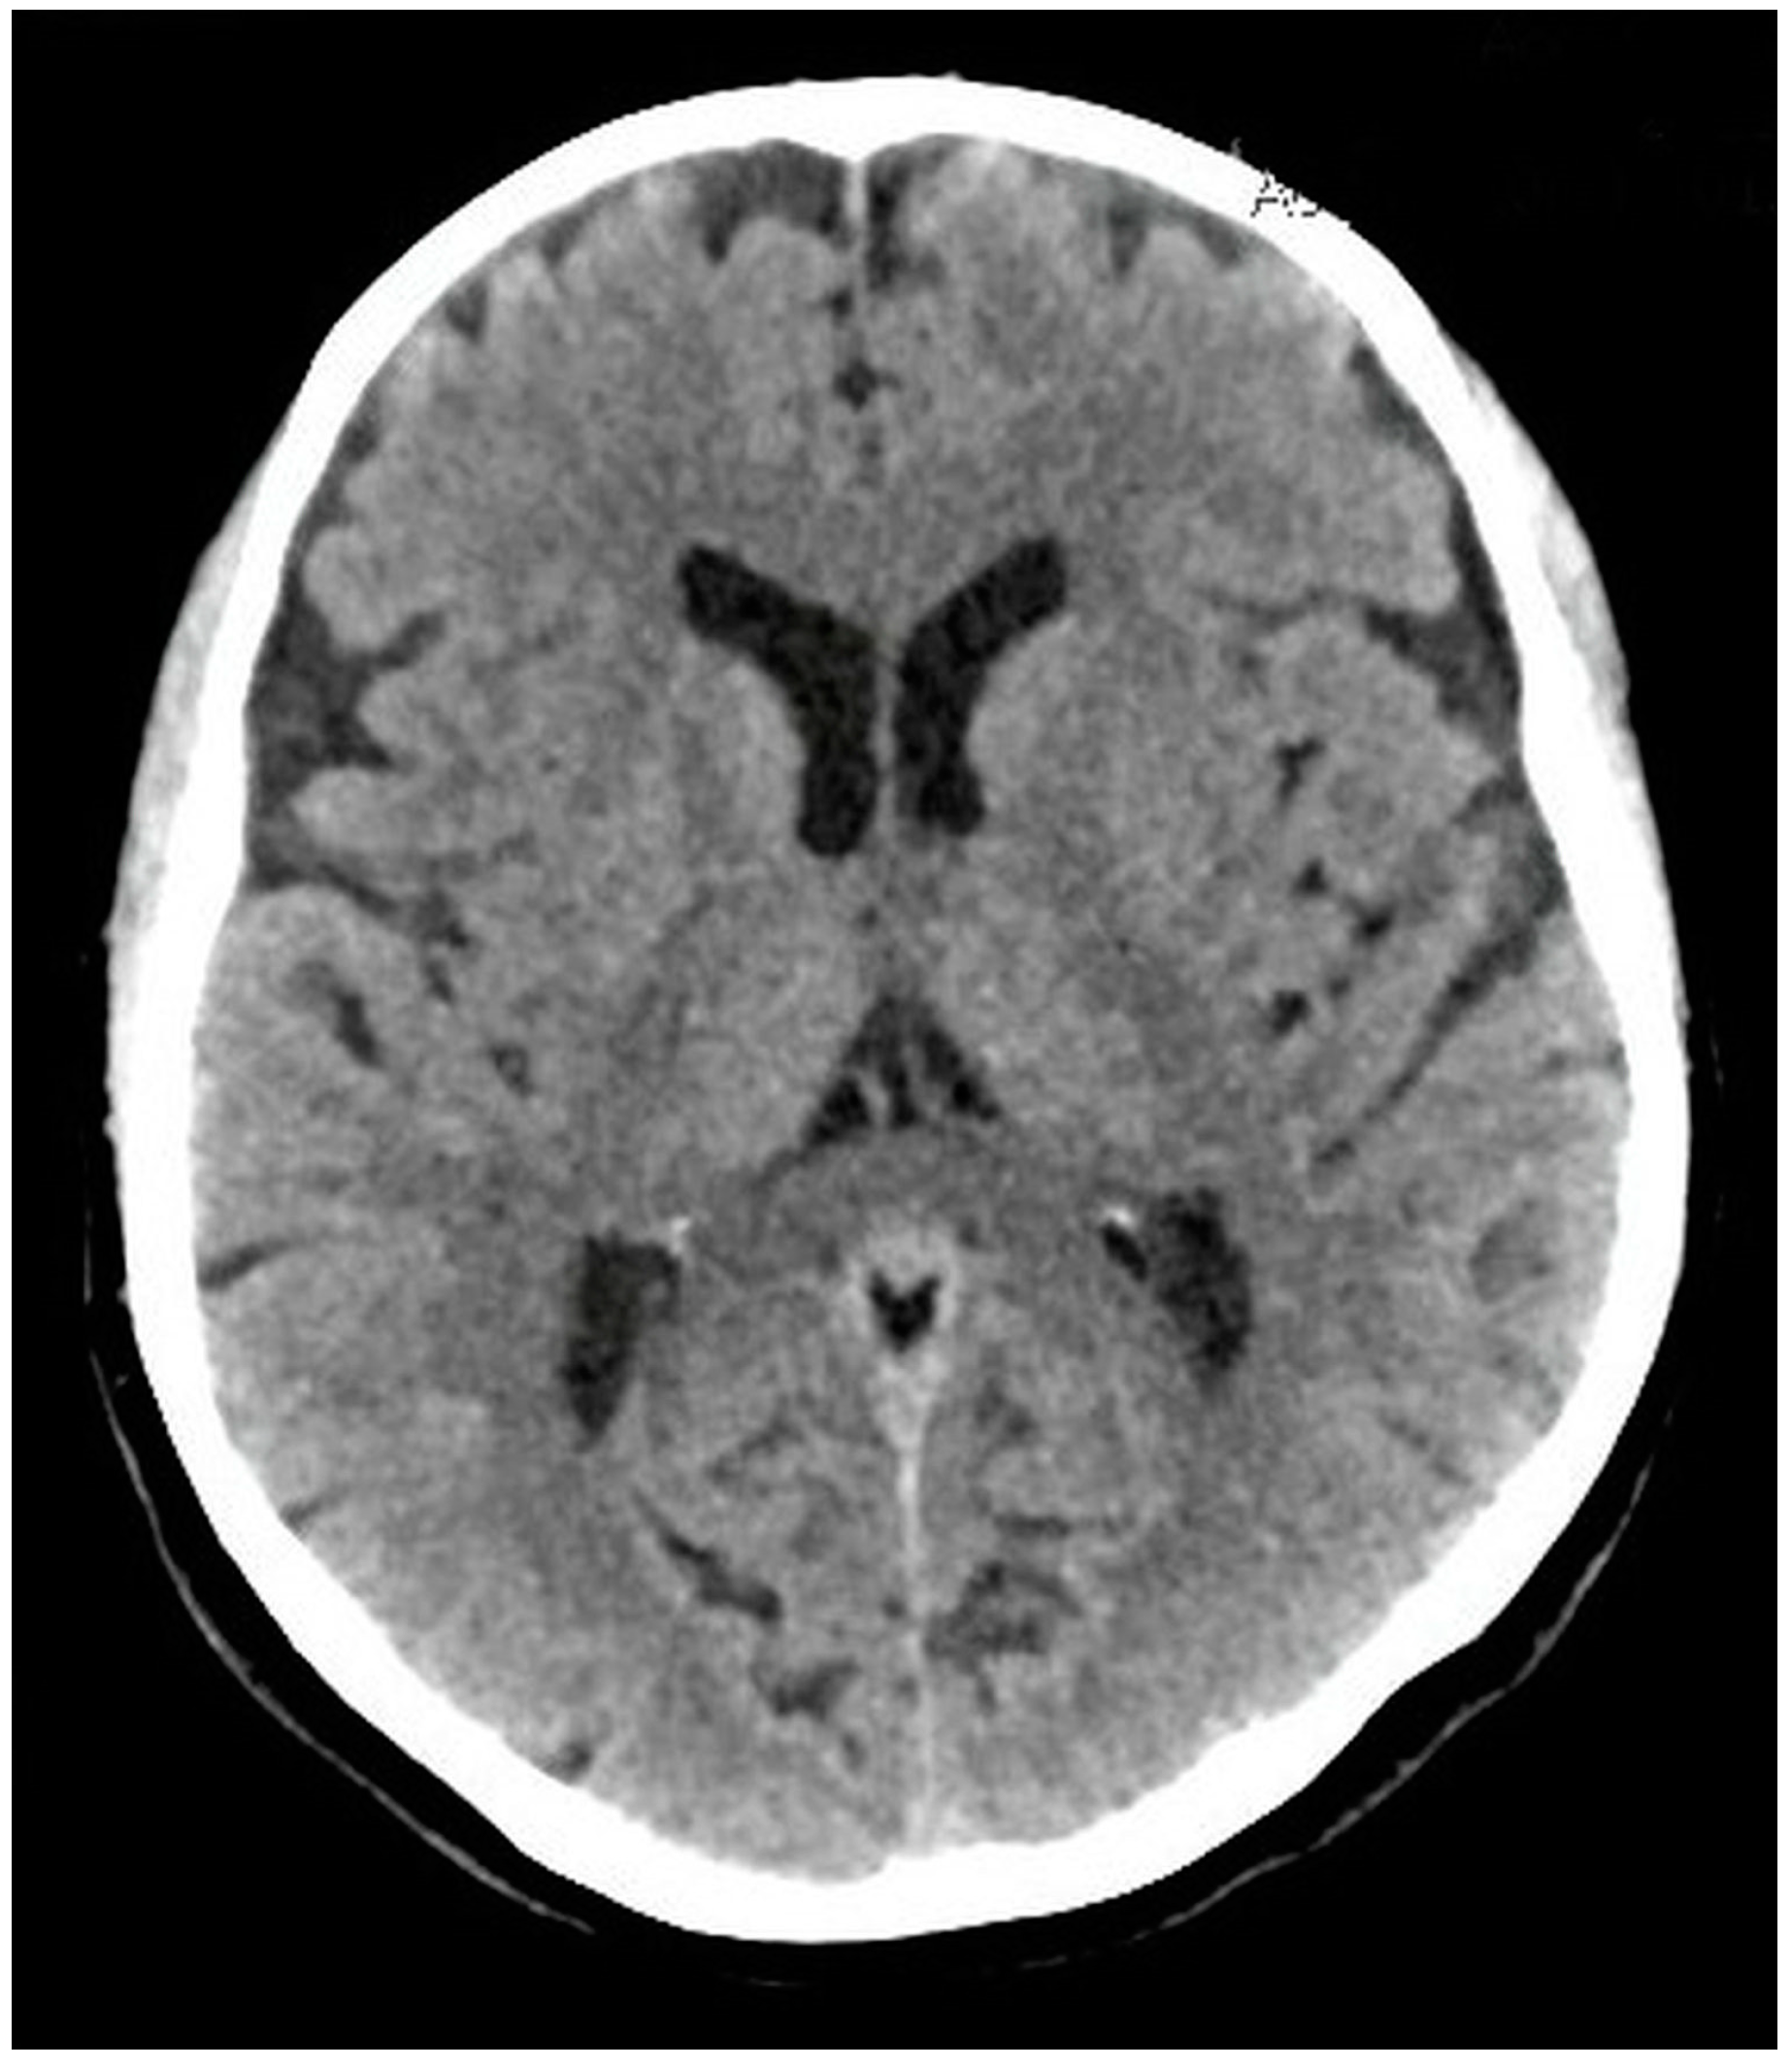

Diagnostic Assessment